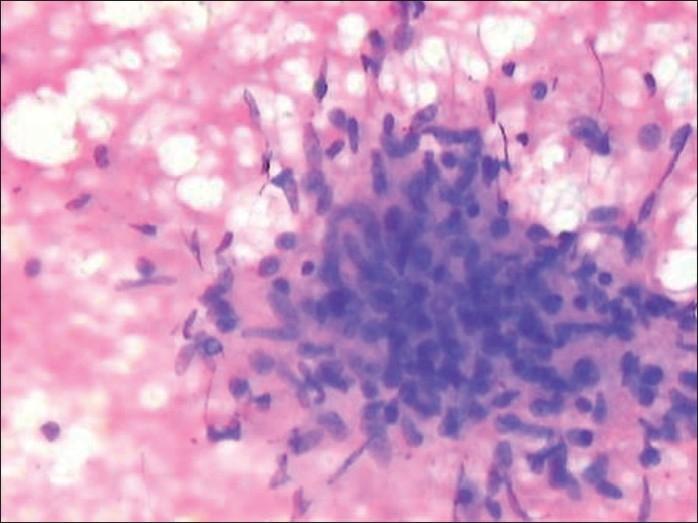

Tuberculosis is a very common disease often presenting in an uncommon form. High level of suspicion is required to diagnose it, thereby preventing its morbidity and mortality. We present a case of young female with multiple tuberculo-protein hypersensitivity reactions without any evidence of active tuberculosis in the body.